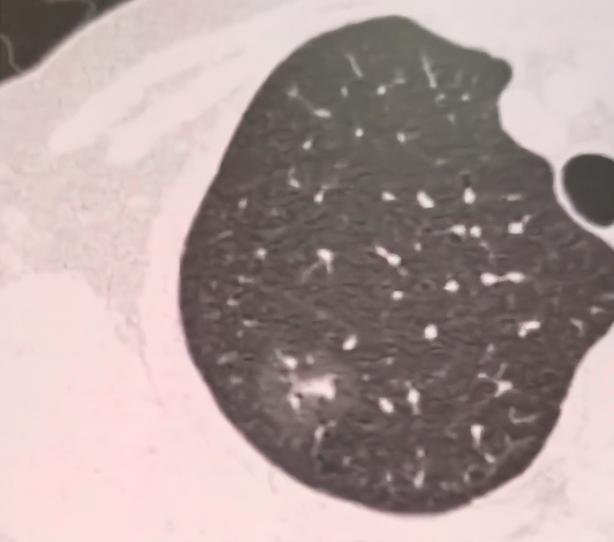

其中最大的一个在左肺,大概1厘米,还是磨玻璃样的,里面能看到血管和空泡,判断大概率也是早期肺癌,建议她定期观察就行。